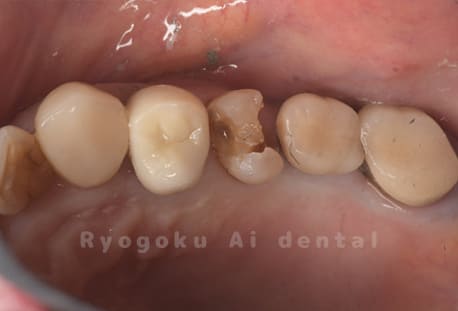

Case08

-

- 原因

- 虫歯

- 治療内容

- セラミックインレー

- 治療費用

- 77,000円

奥歯の黒い点が気になるということで来院された患者さんです。白い詰め物を外したところ、虫歯が中で大きく広がっていたため、患者さんと相談し、セラミックインレーで治療を行いました。

<リスク・副作用>

過度の咬合や衝撃で割れることがあります。